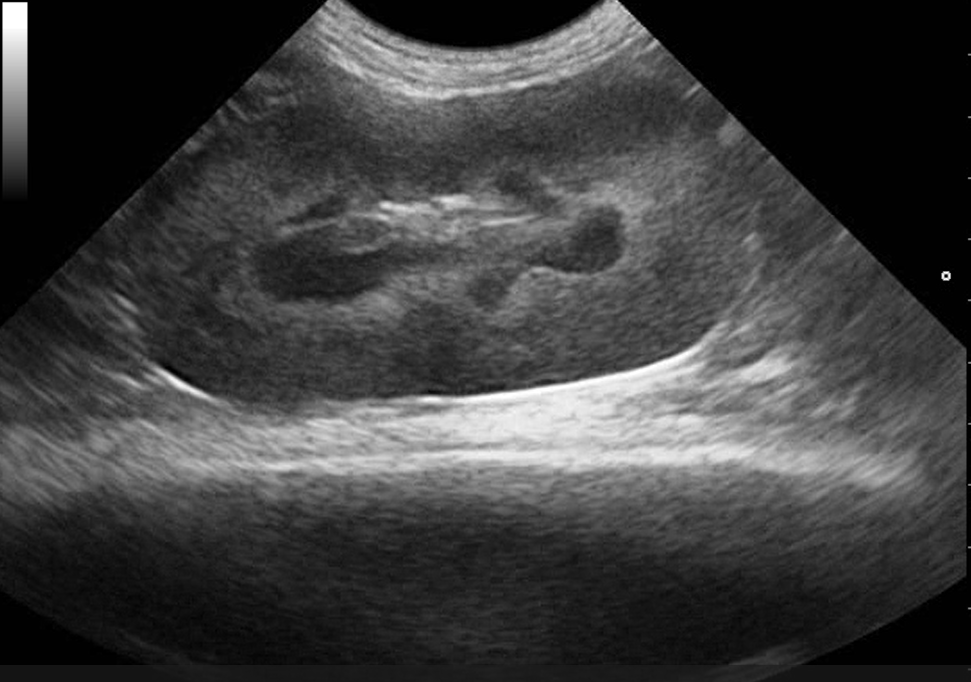

Játra, žlučník